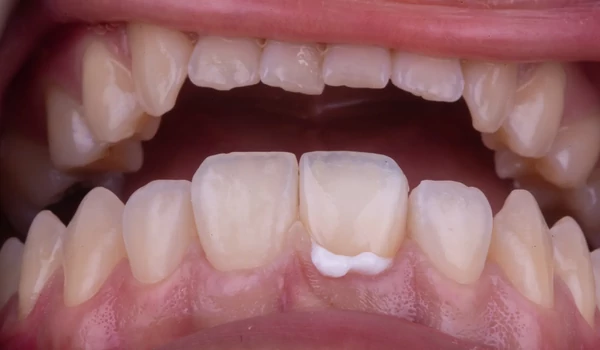

3. Preparáció és digitális lenyomatA végleges restaurációhoz ¾-koronás preparációt végeztek, majd intraorális szkennert használtak lenyomatvételre. Ezt követően ideiglenes koronát készítettek, s árnyalatfotókat is rögzítettek kuraraynoritake.eu. |

14. ábra. Ideiglenes restauráció a helyén. |